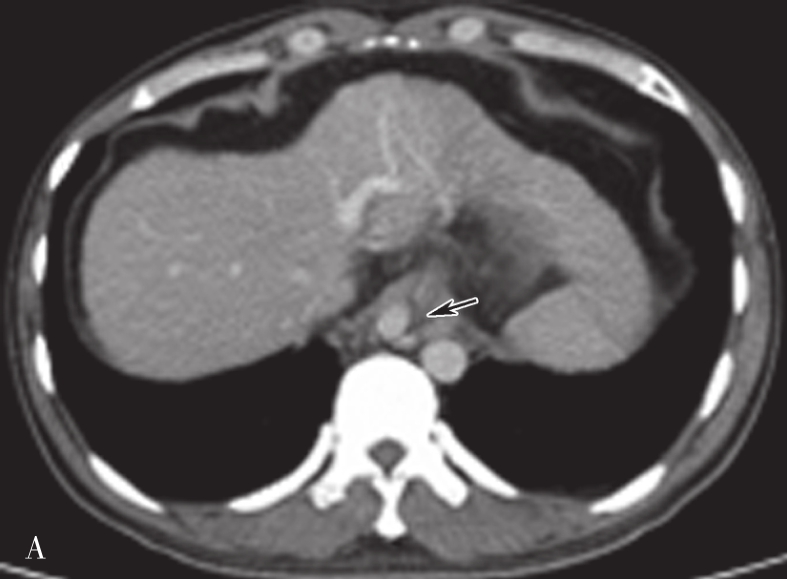

(1)肝脏大小、形态:

在不同层面CT横断面图像,肝脏形态各异。在靠近横膈肝顶部,呈类圆形或椭圆形,面积小,占据腹腔的右半(图5-21-36A);在肝中部或肝门附件,近似楔形,面积较大,占据右侧腹腔(图5-21-36B);在肝下部形态类似于梭形或半月形(图5-21-36C)。

图5-21-36 正常肝脏CT表现